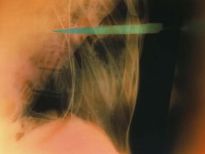

Bu röntgenler gerçek!